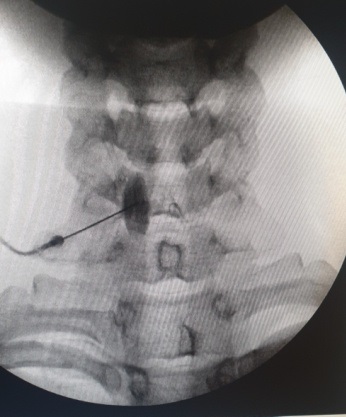

Τι είναι ο οσφυϊκός συμπαθητικός αποκλεισμός

Τα οσφυϊκά συμπαθητικά γάγγλια εκτείνονται από τον πρώτο έως και τον πέμπτο οσφυϊκό σπόνδυλο. Διασχίζουν και τις δύο πλευρές της σπονδυλικής στήλης και παρέχουν τις αισθήσεις των κάτω άκρων. Ο οσφυϊκός συμπαθητικός αποκλεισμός μπορεί να χρησιμοποιηθεί σε περιπτώσεις πόνου στα κάτω άκρα από διαβητική νευροπάθεια, τραυματισμό νευρικών δομών, ακρωτηριασμό, μεθερπητική νευραλγία και αντανακλαστική συμπαθητική δυστροφία. Ο οσφυϊκός συμπαθητικός αποκλεισμός αναισθητοποιεί τα συμπαθητικά νεύρα που μεταφέρουν επώδυνα ερεθίσματα και βελτιώνει την κυκλοφορία στα αιμοφόρα αγγεία των κάτω άκρων μέσω πρόκλησης αγγειοδιαστολής. Η τεχνική θεωρείται ασφαλής με χαμηλά ποσοστά επιπλοκών. Στις πιθανές επιπλοκές ανήκουν ο πόνος στη μέση, η κεφαλαλγία, ο τραυματισμός αγγείων ή νεύρων και η αλλεργική αντίδραση στα φάρμακα.